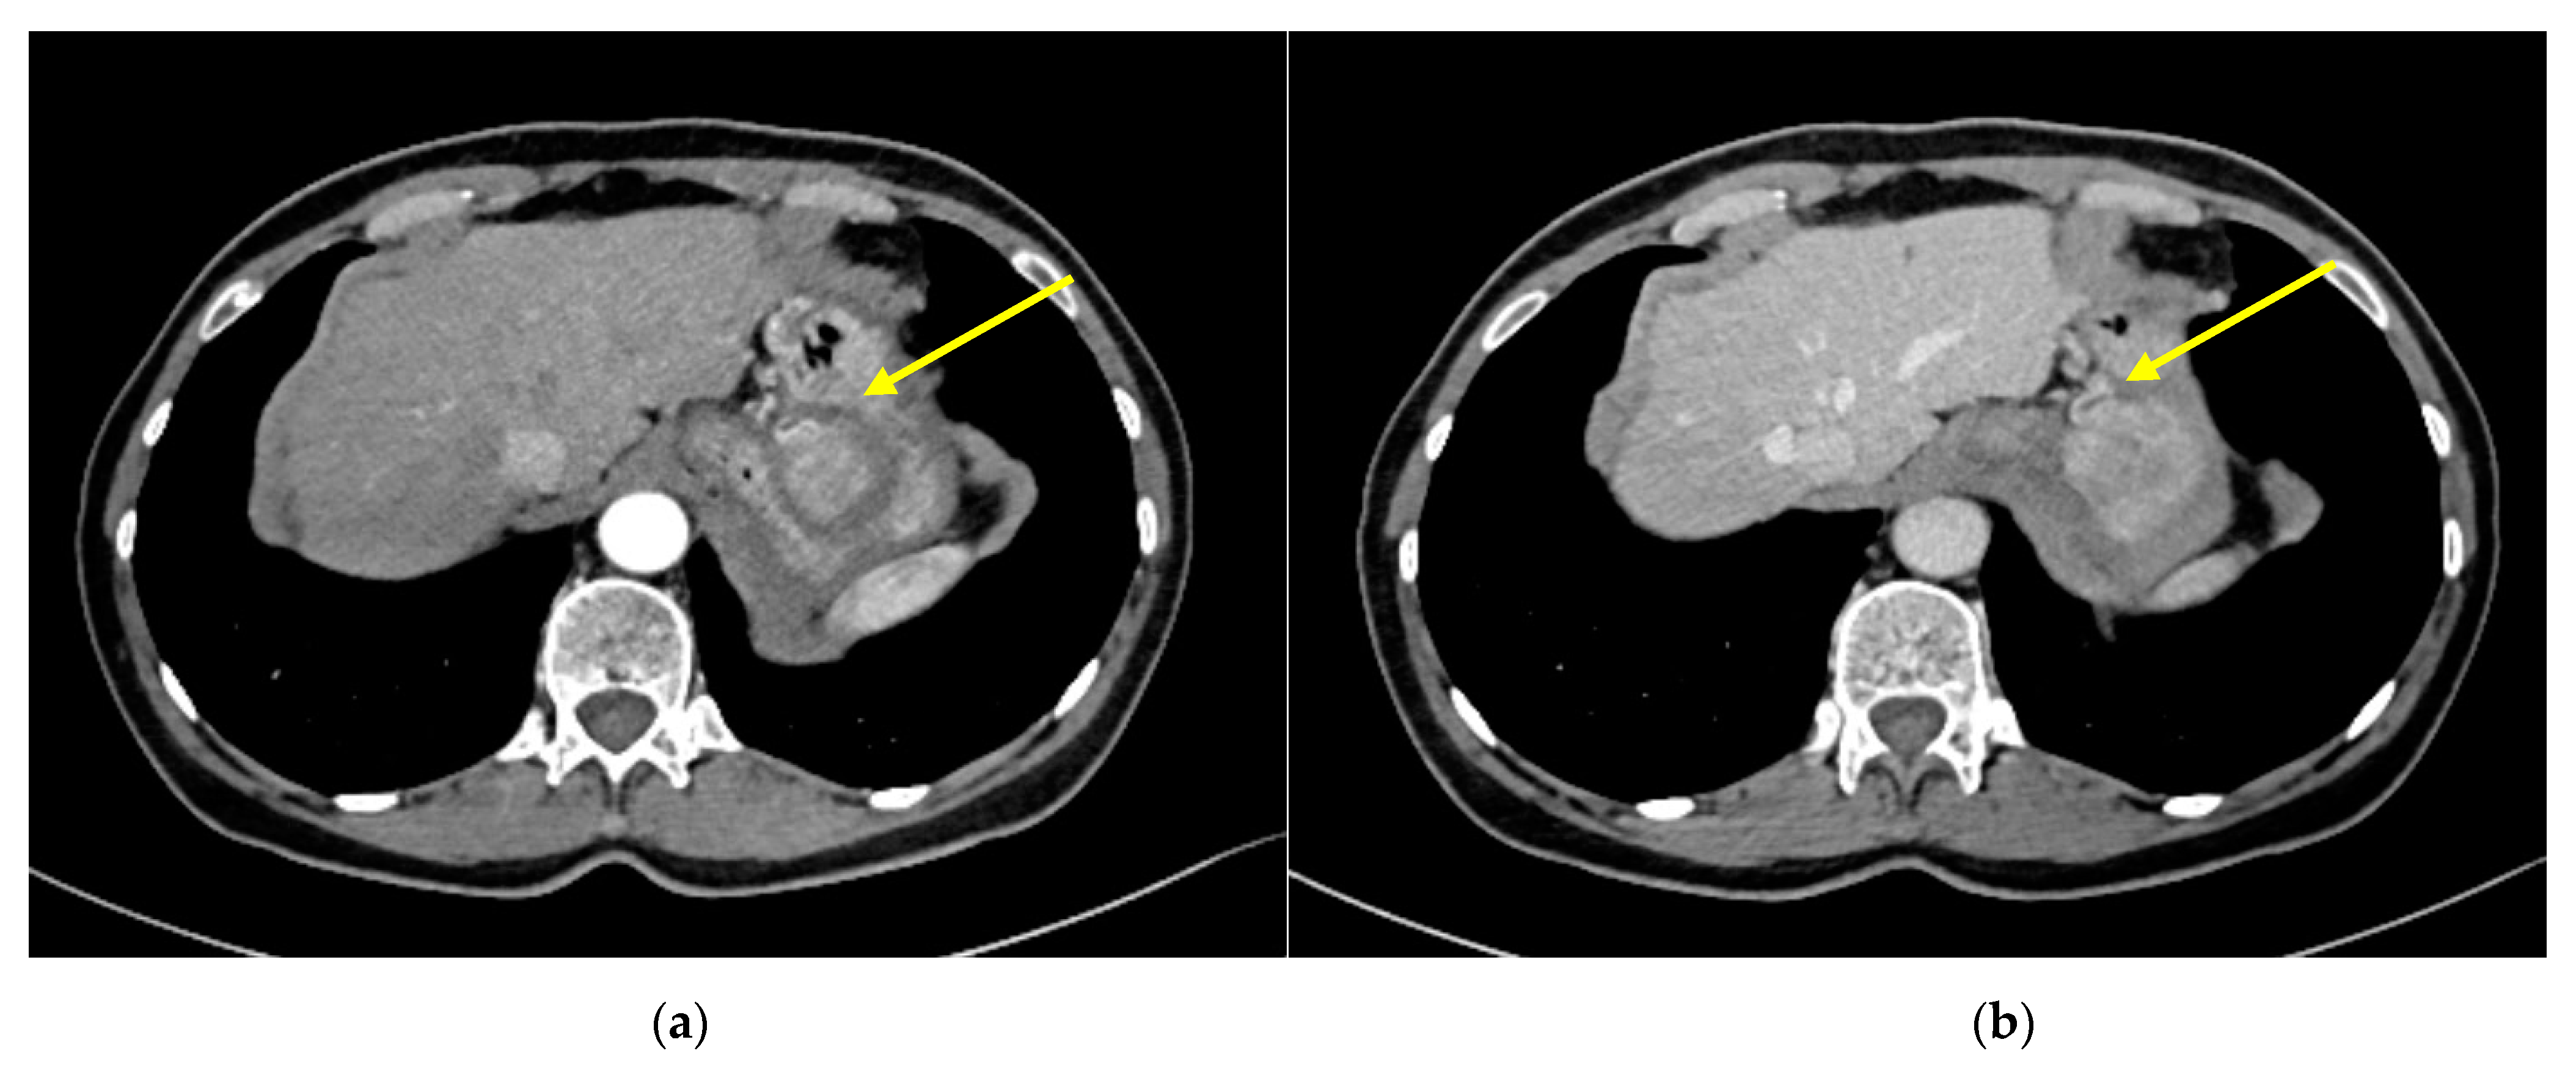

2. Case Report